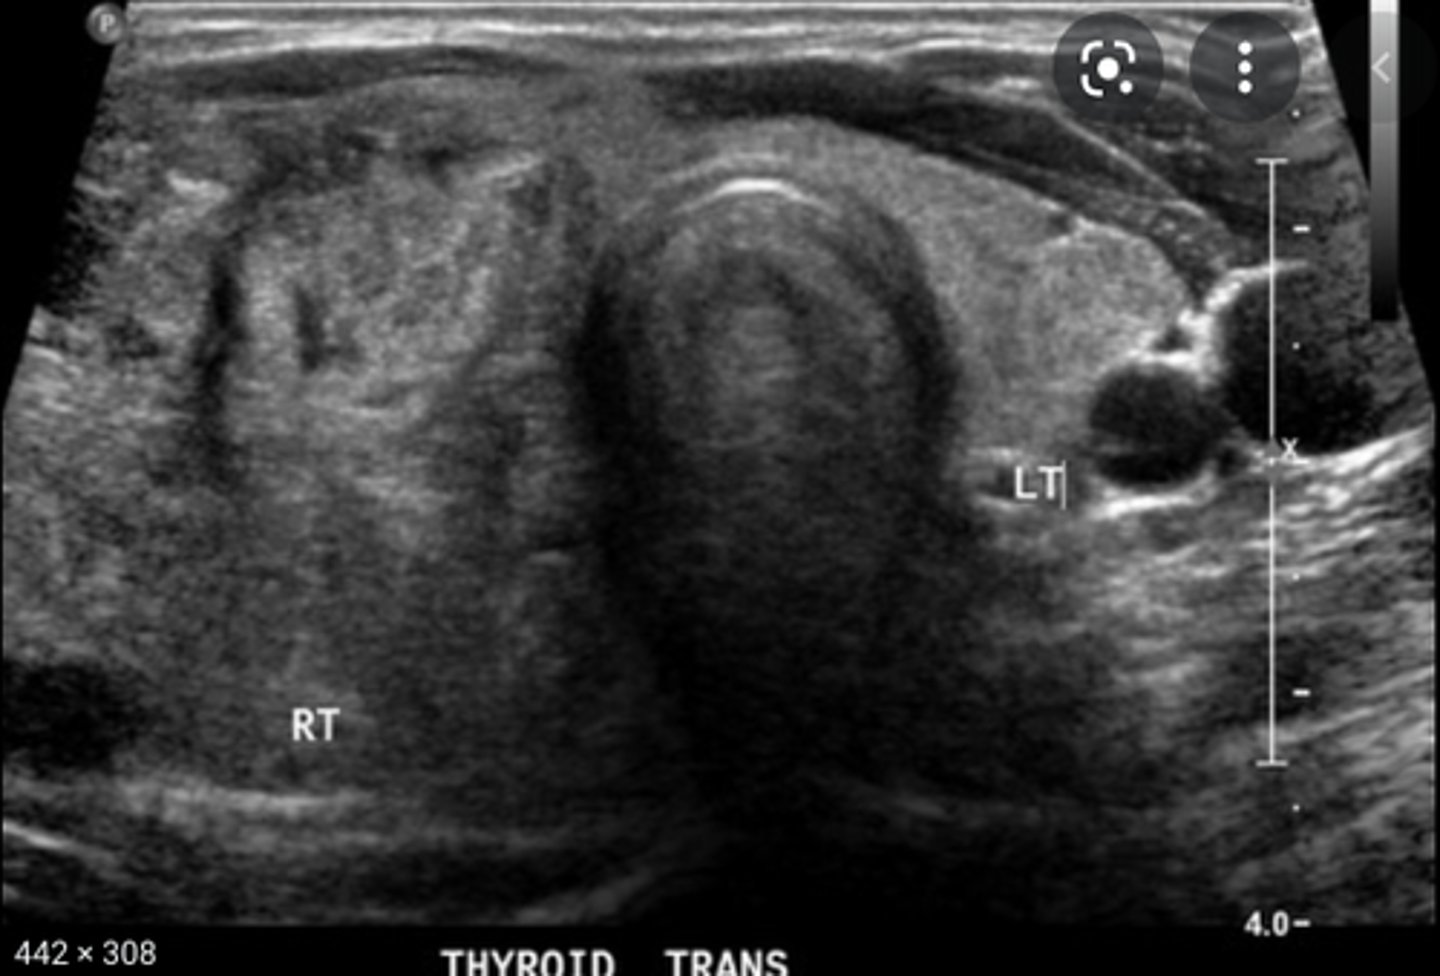

Sonographic Appearance:

-Thyroid lobes and isthmus appear as ____geneous solid structures demonstrating a medium-gray echo pattern with a surrounding thin ____echoic line

-Sternocleidomastoid muscle are _____ and oval in shape appearing ____echoic compared with the normal thyroid gland

-Strap muscles are _____ and ____echoic compared with the normal thyroid gland

-Longus colli muscles appear ____echoic compared with the normal thyroid gland

-Thyroid lobes and isthmus appear as homogeneous solid structures demonstrating a medium-gray echo pattern with a surrounding thin hyperechoic line

-Sternocleidomastoid muscle are large and oval in shape appearing hypoechoic compared with the normal thyroid gland

-Strap muscles are thin and hypoechoic compared with the normal thyroid gland

-Longus colli muscles appear hypoechoic compared with the normal thyroid gland

Anatomy of the Thyroid Glands:

-Largest _____ gland in the human body

-Divided into the right and left lobes with a connecting _____

-_____ lobe is usually larger than the _____

-Isthmus connects the _____ third of the thyroid lobes

-Consists of follicles, connective tissue, nerves, lymphatics, and stroma

-Covered by two layers of _____

-Largest endocrine gland in the human body

-Divided into the right and left lobes with a connecting isthmus

-Right lobe is usually larger than the left

-Isthmus connects the lower third of the thyroid lobes

-Covered by two layers of connective tissue